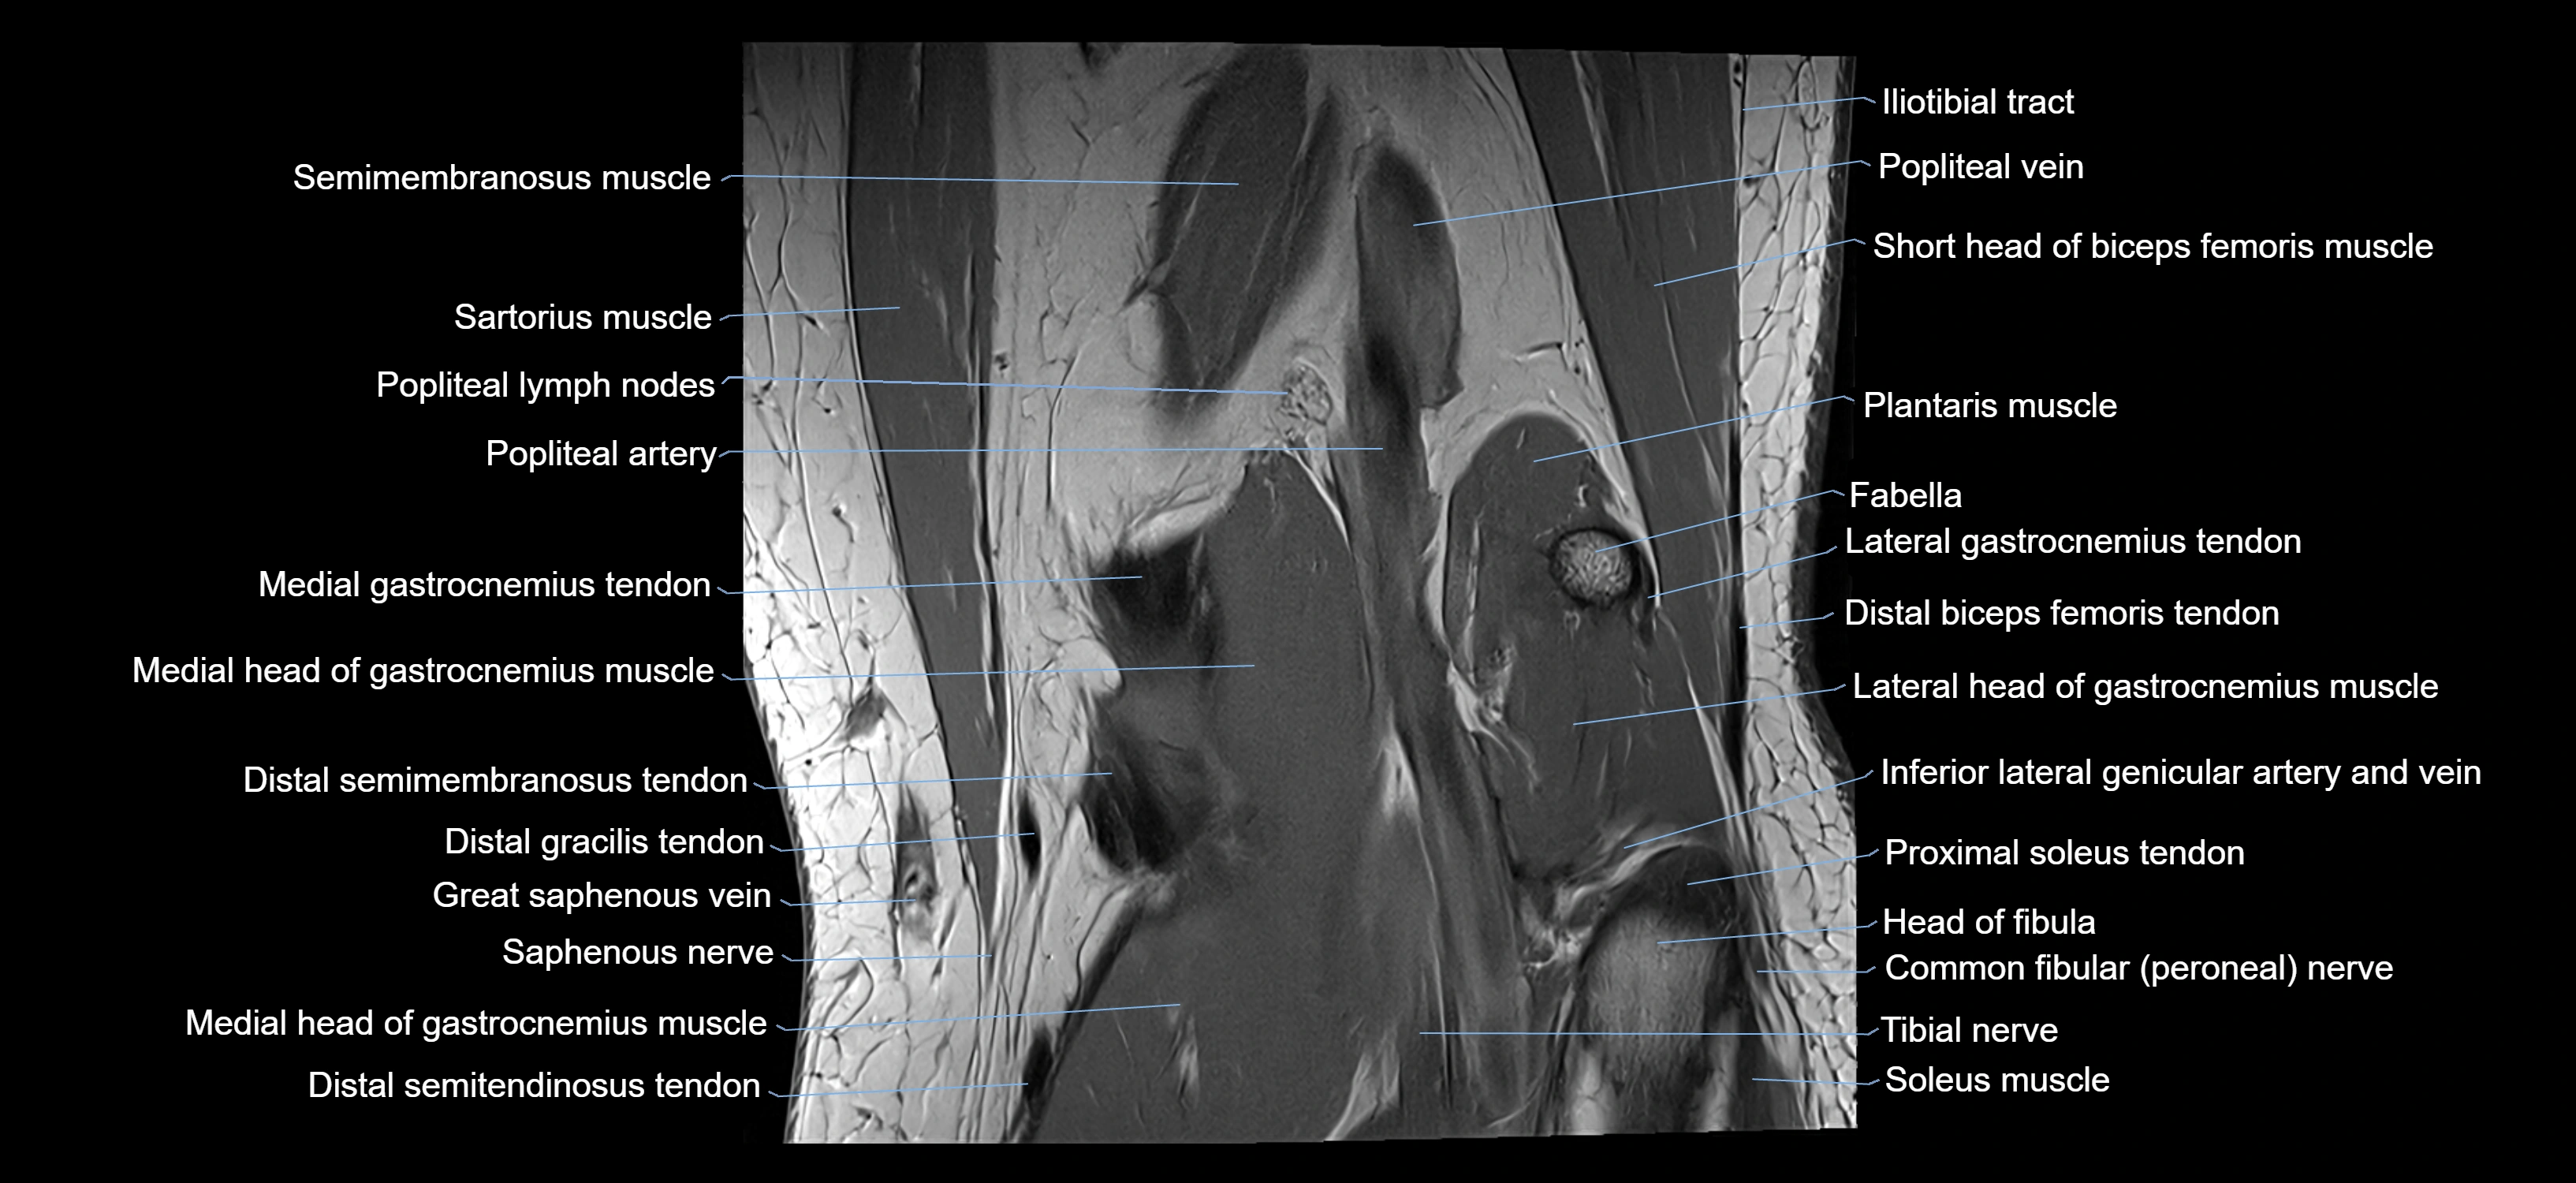

- Popliteal artery

- Popliteal lymph nodes

- Popliteal vein

- Saphenous nerve

- Sartorius muscle

- Semimembranosus muscle

- Soleus muscle

- Tibial nerve